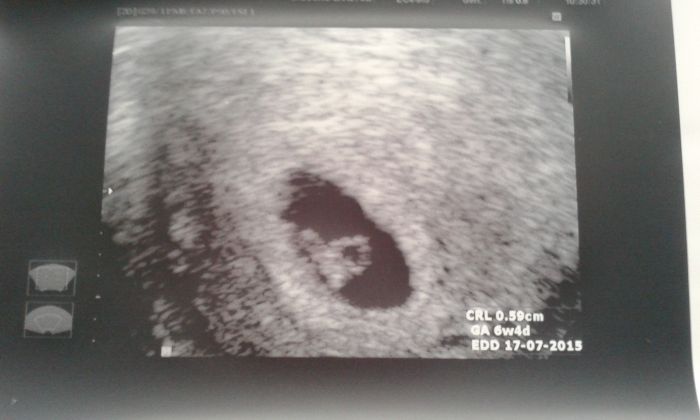

Jinak obrázky už mam dva, z první kontroly v 8mem týdnu a pak z 9teho, je tam jen takovej flíček.

Na kontrolu jdu v pondělí a dostanu průkazku a protože si nejsem jistá,jestli jsem se skoro před 14ti dny pochlubila,tak se pochlubím i teď.